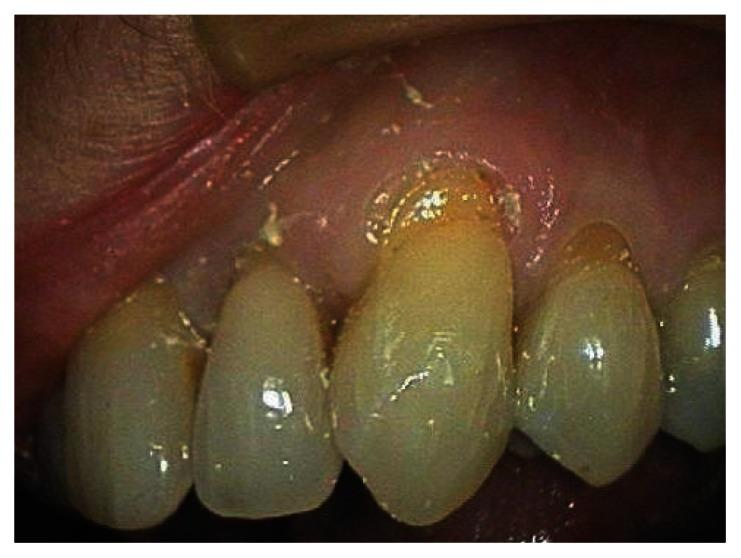

This case report describes the treatment of a maxillary canine that had 4 mm of marginal gingival recession. The exposed root had been previously restored with a composite class 5 restoration. The restoration was removed and the root planed and demineralized. The root was then covered by a subepithelial connective tissue graft harvested from the palate. The flap was coronally positioned to completely cover the graft and exposed root. The healing was photographed post-operatively at one month, six months, and seven years. Root coverage increased to 100% after seven years. The zone of attached gingiva also increased.